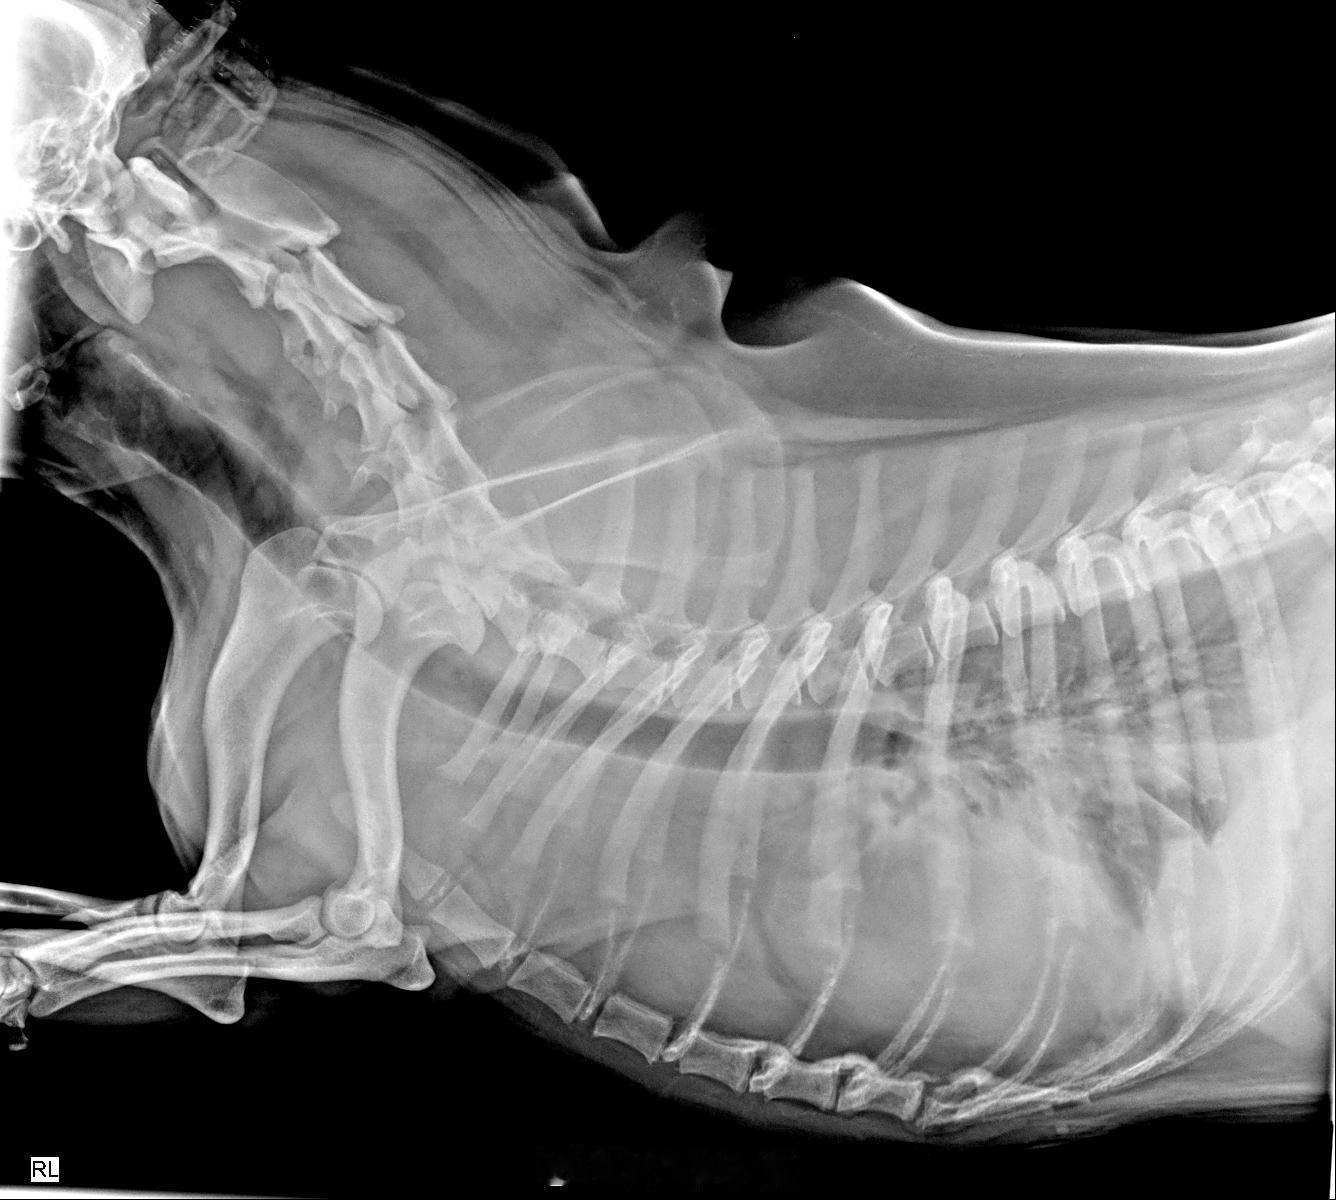

怀疑是间质细胞瘤,恶性特征明显